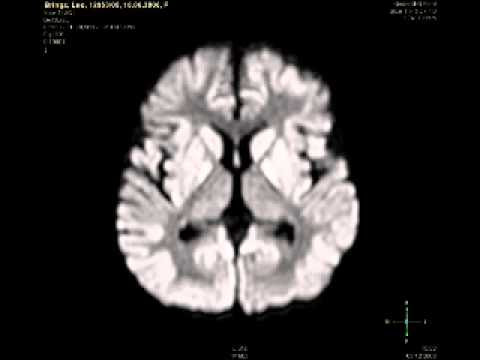

YOUTUBE : first autologous cord blood therapy of cerebral palsy - part 6: brain mri (b) axial flairdwi - brainmri (flair dwi sequences with contrast media).brainmri (flair dwi sequences with contrast media).brainmri (flair dwi sequences wit ...

YOUTUBE : first autologous cord blood therapy of cerebral palsy - part 5: brain mri (a) axial flair - brainmri (flair sequences).brainmri (flair sequences).brainmri (flair sequences) of a 2.5 years old patient (l.b.) 14 days after global ...